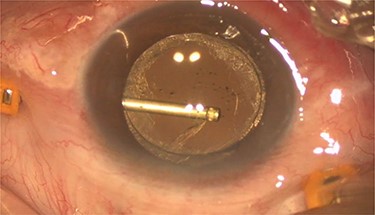

Pars plana vitrectomy and posterior capsulotomy were done. After placing three 23-gauge trocars, a corneal paracentesis was made. After IOL tapping, the entrapped turbid fluid escaped to the anterior chamber (Fig. 3). Anterior vitrectomy and posterior capsulotomy were done using a 23-gauge vitrector (Fig. 4).

Intra-operative photo showed the posterior capsulotomy using 23G vitrector.